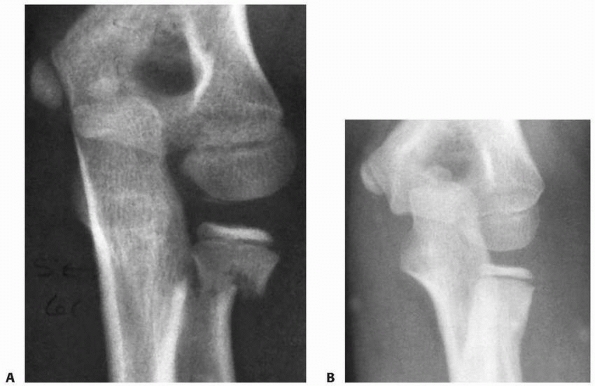

associated with elbow dislocation, the head fragment is totally

displaced from the neck.5,13,27,42,70,118

The proposed mechanism is a fall on the hand with the elbow flexed,

which causes a momentary partial dislocation of the elbow and forces

the radial head posterior to the capitellum.

suggested that displacement and fracture occurred during spontaneous

reduction of the transiently dislocated elbow. During this reduction

process, the capitellum applies a proximal force to the distal lip of

the radial head, causing it to separate as the forearm and distal

radius are reduced distally (see Fig. 11-8A).

The radial neck and olecranon return to their anatomic locations while

the radial head remains in the posterior aspect of the joint.118